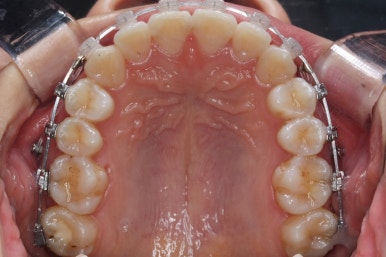

이제 치열은 거의 가지런해졌습니다.

치열이 가지런해졌다는 뜻은 이제 곧 뒤로 당기기가 가능해졌다는 뜻이기도 합니다.

우선 윗니가 먼저 가지런해졌기 때문에 윗니부터 뒤로 당기기 시작합니다.

연산동교정치과에서 이번에 진행한 방법은 비발치교정이기 때문에 미니스크류를 잇몸뼈에 식립합니다.

위 사진에서 화살표 부분이 미니스크류인데요.

어금니쪽 잇몸에 아주 작은 나사가 보이실텐데요. 이것을 이용해서 전체 치열을 뒤로 당겨넣습니다. 물론 사랑니는 제거가 된 상태입니다.